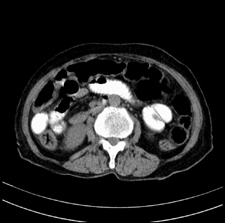

患者,女,75岁。腹痛,体黄5日,膝胸位时腹痛缓解。肝功能明日出来。彩超提示胆总管占位,未见血流信号。心电图提示s-t段改变。患者体质较弱,未能增强。

胆总管结石

胆总管多发结石

胆总管多发结石伴肝内外胆管轻度扩张。

胆总管上段,腔内有软组织密度影 ,ct值36-44hu。大家看有没有胆管癌的可能。

典型胆总管多发结石;增强扫描前后ct值是否发生改变是鉴别结石与占位的依据。